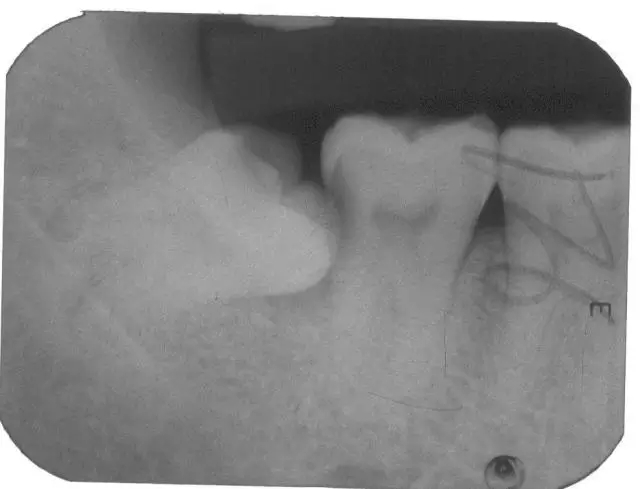

齿哥 由于人类长期进化过程中,挑选食物越发精细,咀嚼力日益下降,而使颌骨发育退缩,颌骨与牙齿退化量不协调,导致颌骨缺乏足够空间容纳全部恒牙,牙弓后端无足够空间让智齿萌出。(图1 2)

牙妹 专业级别!那拔了智齿会瘦脸吗?(图3)